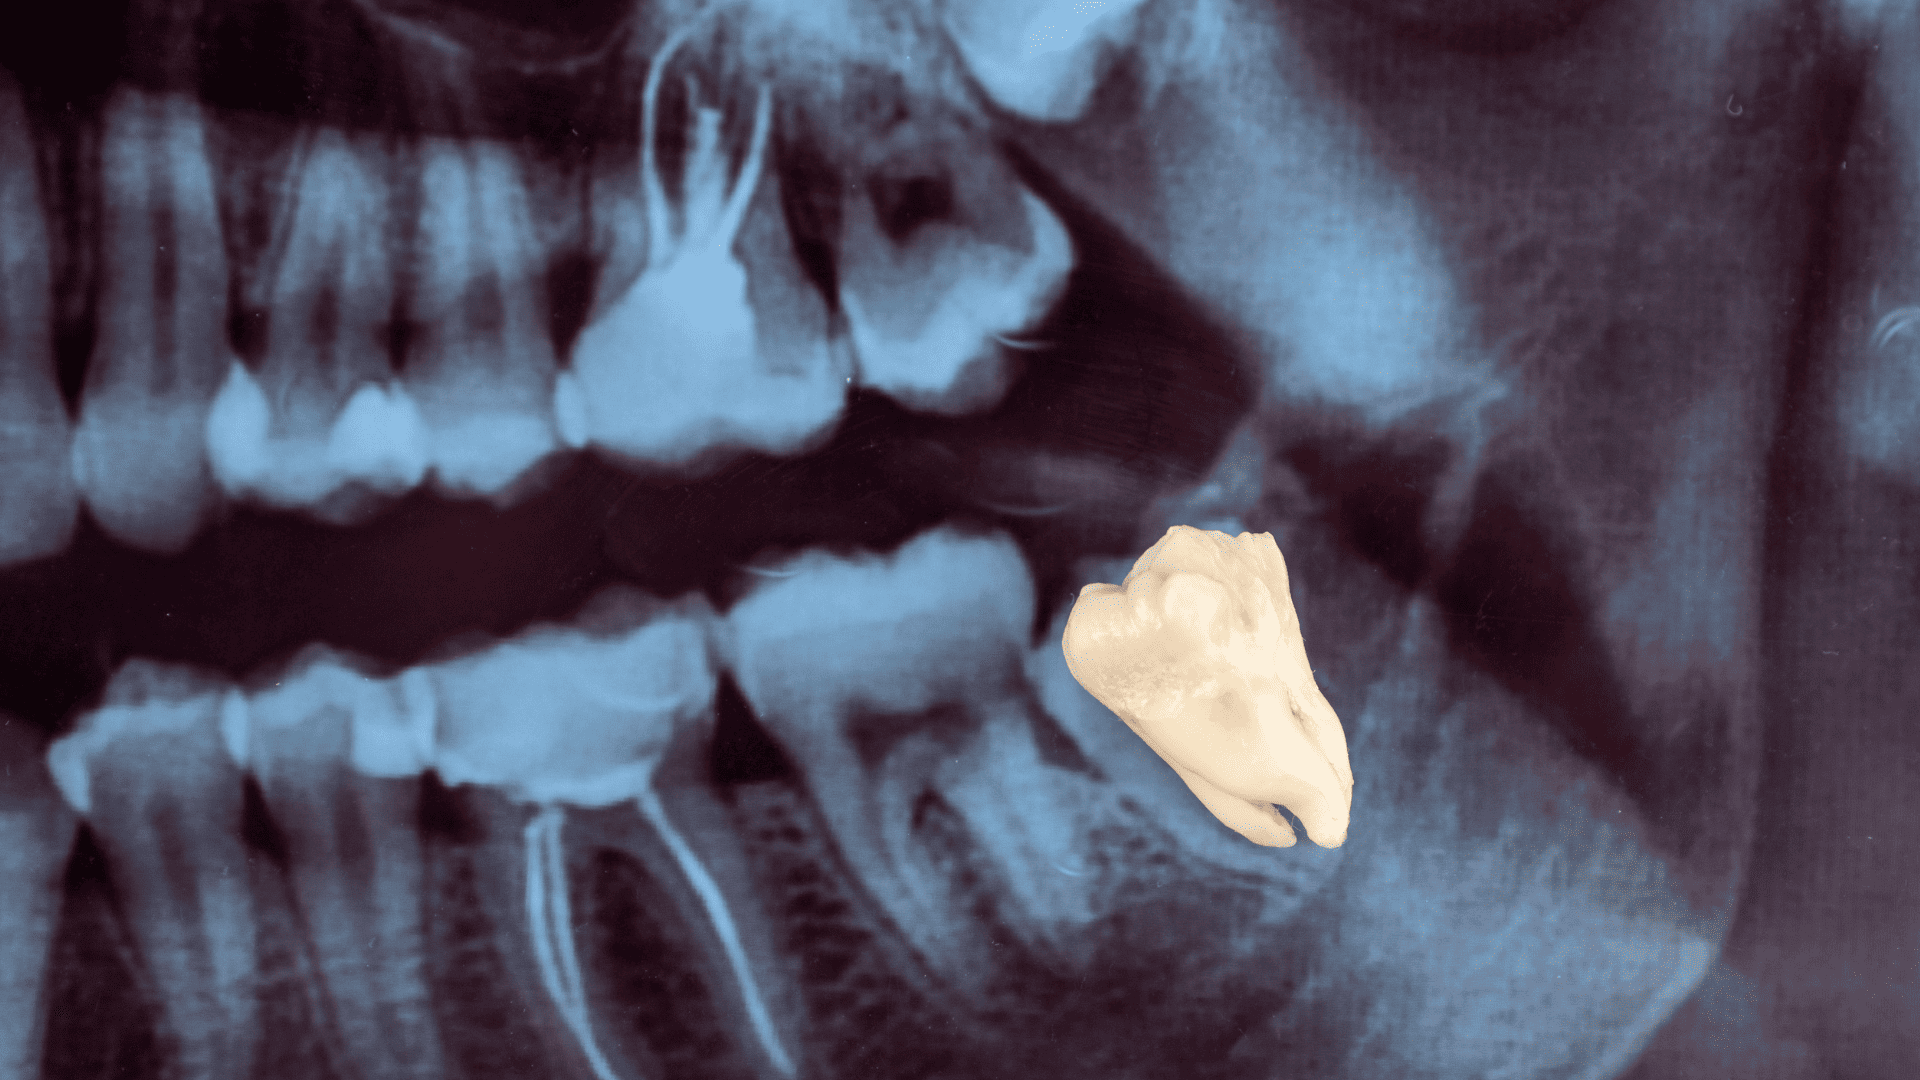

1. Apa itu gigi bungsu?

Gigi bungsu adalah gigi geraham terakhir yang biasanya muncul pada usia remaja akhir hingga awal 20-an. Banyak orang mengalami masalah dengan gigi bungsu karena posisi tumbuhnya yang tidak ideal, sehingga dapat menyebabkan rasa sakit, infeksi, atau kerusakan pada gigi di sekitarnya. Kalau kamu merasakan gejala seperti nyeri hebat atau pembengkakan, sebaiknya konsultasikan dengan dokter gigi untuk menentukan apakah perlu dilakukan pencabutan atau tidak.